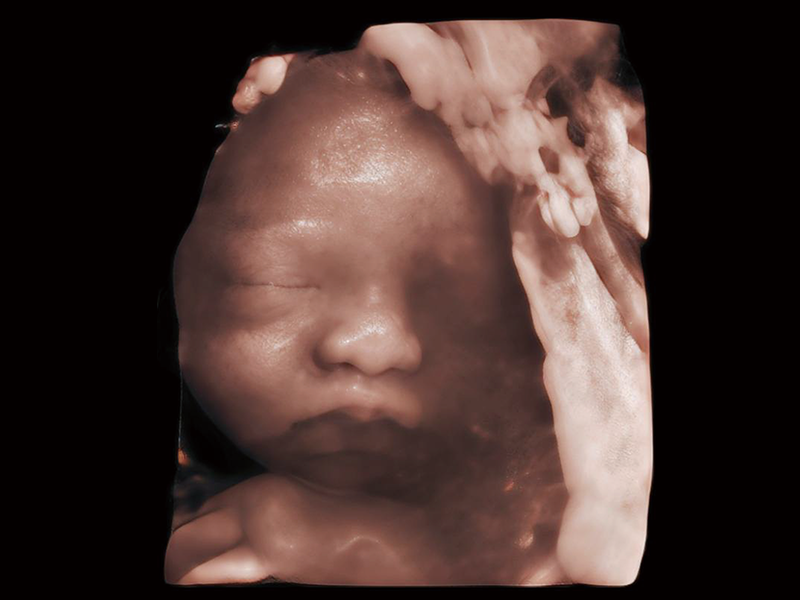

HD Portrait

S-Live Studio

S-Fetus 5.0